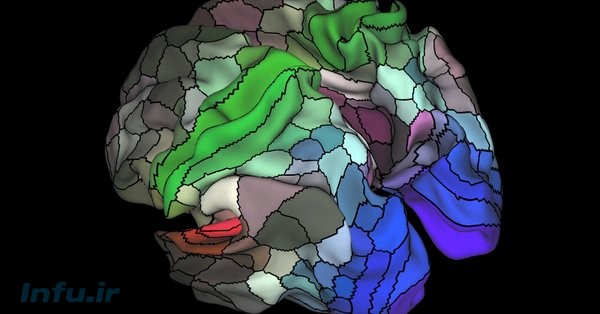

یک نقشه تازه از مغز، نزدیک به صد منطقه تازه در این عضو حیاتی بدن را برای نخستین بار نشان میدهد.

مغز همانند یک گستره پر از چین و چروک است. اما در حقیقت مغز به سرزمینهای نامرئی زیادی تقسیم شده است. هر کدام از این بخشها مسئول انجام کاری در مغز هستند. گروهی از این عصبها وقتی ما چهره آشنایی میبینیم فعال میشوند و به یاد ما میآورند که این چهره را قبلا کجا دیدهایم. گروهی دیگر در هنگام خواندن، گروهی در هنگام دیدن و گروهی هم مسئول حرکات اعضای مختلف بدن هستند.

به تازگی محققان نقشه تازهای از مغز انسان را منتشر کردند که به عقیده متخصصان نقطه عطفی در دانش عصب شناسی بهشمار میآید. این نقشه نزدیک به صد منطقه تازه در مغز را که قبلا شناسایی نشده بود، نشان میدهد.

به گفته محققان از این پس برای فهمیدن هر جنبهای کار مغز، میتوان به این نقشه راهنما نگاه کرد. با این نقشه میتوان جریان رشد کودکان را درک کرد و همینطور متوجه شد که بیماریهایی مانند آلزایمر با مغز چه میکنند.

اطلاعات لازم برای طراحی این نقشه از صدها مغز مورد مطالعه دریافت شده است. این نقشه از تمام نقشههای مغز موجود بسیار پیشرفتهتر است.